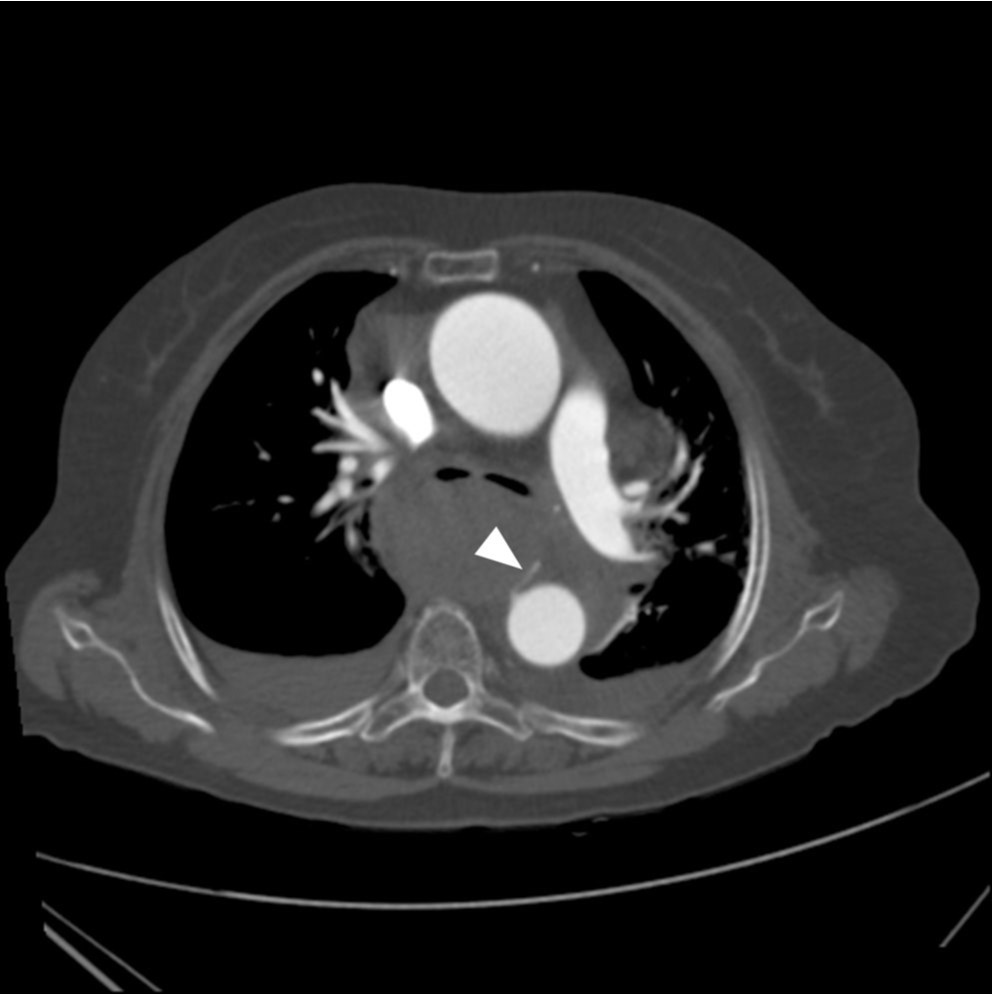

Fig. 2A, B. Axial CT images reveal a large hematoma with extravasation of contrast media (arrow) in the posterior mediastinum. The extravasation was connected with the right bronchial artery (arrowhead) originated from the descending thoracic aorta.